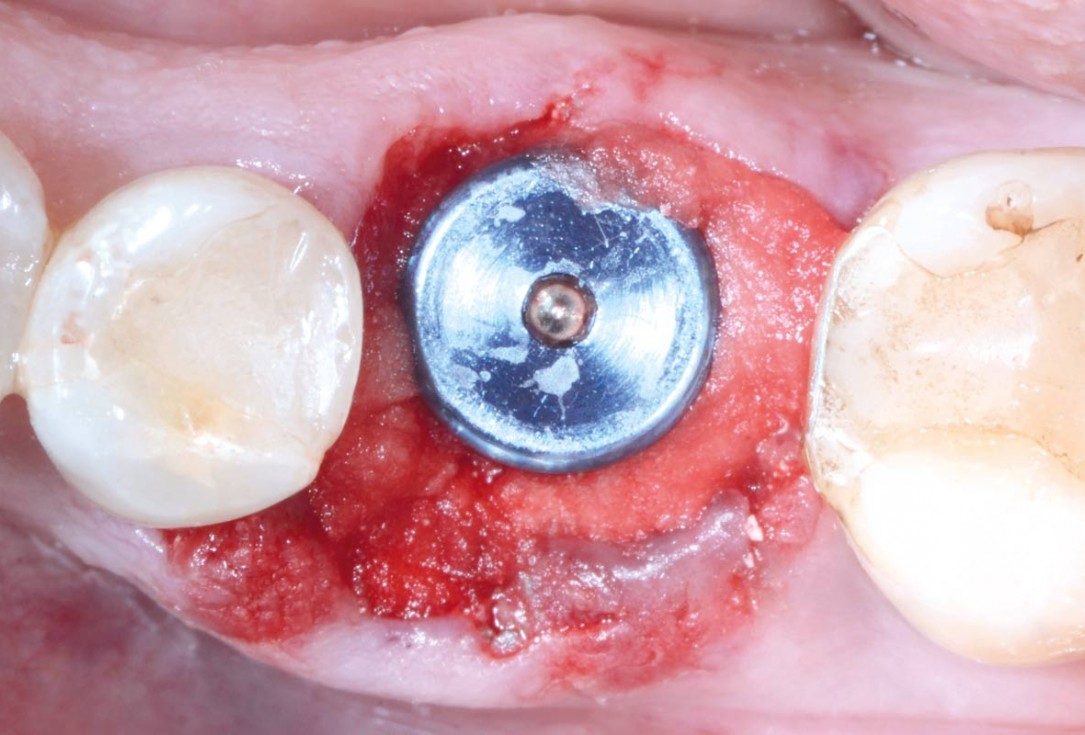

Covering of an immediately placed implant with permamem® - Prof. Z. Mazor

Immediately placed implant covered with permamem®. permamem® passively immobilized by sutures and intentionally left exposed to the oral cavity.